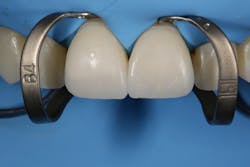

While performing esthetic dentistry, our bonding materials must work as promised to achieve long-term success.2 When manufacturers report bond strengths in the clinical arena, studies are conducted with the rubber dam in place (figures 1 and 2). When etched surfaces are exposed to the oral environment, including expired air while using typical isolation devices, the surfaces are challenged by moisture from numerous sources, causing the adhesive chemistry to be altered. Hence, to achieve the best bond strengths, a well-sealed barrier will help our results, often dramatically.